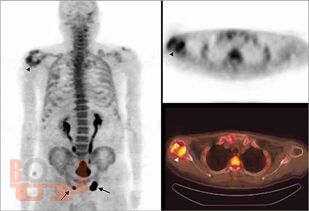

All chapters have been thoroughly revised. The present edition has incorporated 4 new chapters in the musculoskeletal subsections and 2 new chapters in the breast subsection. Content has been divided into 7 different subsections, beginning with current concepts and interventions. The first section deals with all imaging modalities in musculoskeletal imaging. There is an updated section on MR imaging, including new additions of imaging of wrist and ankle; peripheral nerve imaging and imaging of prosthetic joints. The second part of the book contains updated chapters on Breast imaging and interventions and includes two new chapters on Male Breast Imaging and Advances in Breast Imaging. This edition will serve as a concise yet comprehensive guide for students and practitioners of radiodiagnosis as well as a ready reckoner to clinicians in understanding the basics as well as current advances in imaging and interventions.